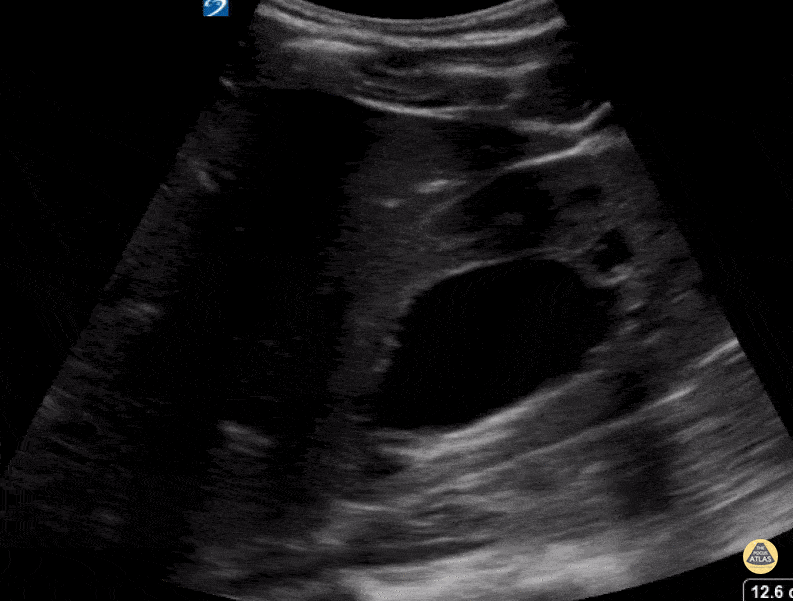

Peds-Genitourinary - Severe Hydronephrosis

16 year old with right sided flank pain. Patient found to have severe hydronephrosis. Contributor: Kathryn Pade, MD